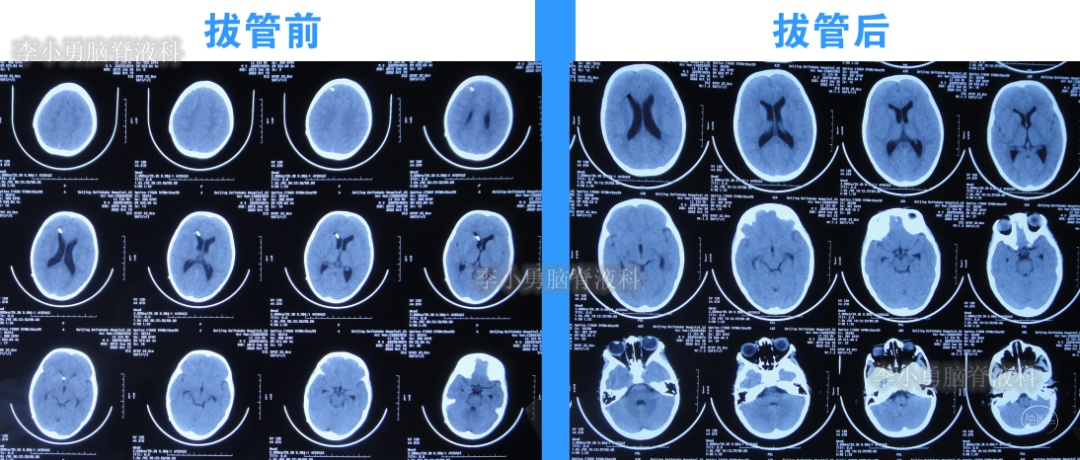

2022年10月19日(住院治疗111天),拔除了脑室引流术,拔管前和拔管后头颅CT(图-18)对比。

图-18:2022年10月19日拔管前后头颅CT对比